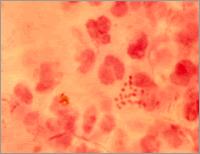

形態與染色淋球菌呈卵圓形或豆形,菌體長0.6~0.8µm,寬約0.5µm。常成對排列,鄰近面扁平或稍凹陷,像兩粒豆子對在一起。無鞭毛,不形成芽孢。在急性感染的機體內,其形態較典型,多位於細胞漿內。慢性期則在細胞外。淋球菌革蘭染色陰性。用鹼性美藍染色時,菌體呈藍色。用Pappehheim Saathof染色時,菌體呈紅色,背景為天藍色,十分清晰。